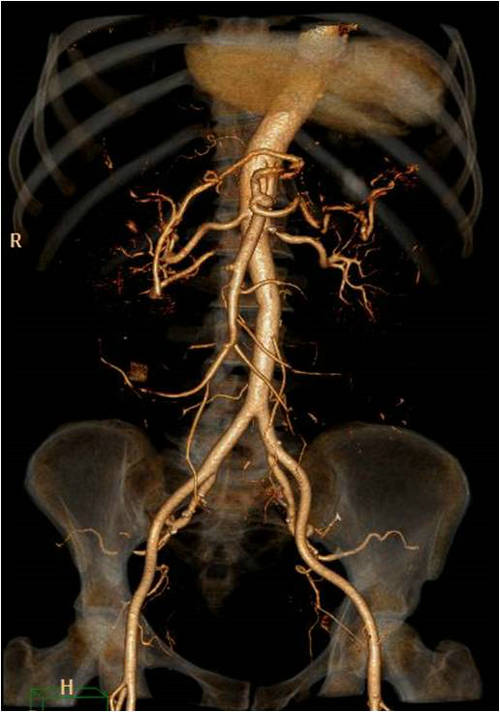

尚老太太今年84岁高寿, 1天前吃了个橙子后,突然出现腹痛、腹泻症状,被子女连夜送到郑大五附院消化内科。王长武副主任医师立即进行检查,在排除了急性胰腺炎、阑尾炎、胃肠炎后,当机立断做了腹部动脉CTA,结果发现肠系膜上动脉堵了,立即请血管外科医师会诊,急转该科。王兵副院长、崔文军副主任指导值班医生马上完善术前检查,紧急进行手术。

由于患者年龄大,冠心病、房颤20多年,基础情况差,术前请心内科关李华副主任及手术室闵娜医师前来会诊,给予制定围手术期处理意见。手术麻醉由胡强夫主任亲自进行,王兵副院长主刀。手术开始后发现肠管已经缺血发绀,幸运的是诊治及时,还未出现坏死迹象,腹腔也没有腹水。将肠系膜上动脉游离出来,取栓管取出的血栓将近10cm。缝合血管恢复血流后,肠管立即恢复红润,蠕动也明显改善。

急性肠系膜上动脉栓塞是由于栓子进入肠系膜上动脉造成阻塞所致,发病凶险,死亡率极高,最高可达88%—98%,症状表现为“Bergan三联征”:①突发腹部剧烈疼痛,药物不能缓解,早期腹软不胀,肠鸣音活跃,症状与体征不符;②器质性或并发房颤的心脏病,如房颤、风湿性心脏病、感染性心内膜炎、近期心梗病人;③胃排空障碍表现如腹泻、血便。该病的诊断非常困难,误诊率高达90%—95%,往往以阑尾炎、急性胃肠炎等疾病误诊,耽误了最佳治疗时间。肠管对缺血的耐受时间约12小时,尽早确诊并手术是降低死亡率的关键,患者肠道还有修复的可能性。缺血时间过长的患者肠道坏死,大量的肠毒素吸收、大量液体渗出导致患者很快出现中毒性休克,严重威胁生命。手术需要将肠道切除,导致“短肠综合征”。这类病人由于缺乏足够的肠管吸收营养,需要支付高额的全静脉营养费用,严重影响患者的生活质量。